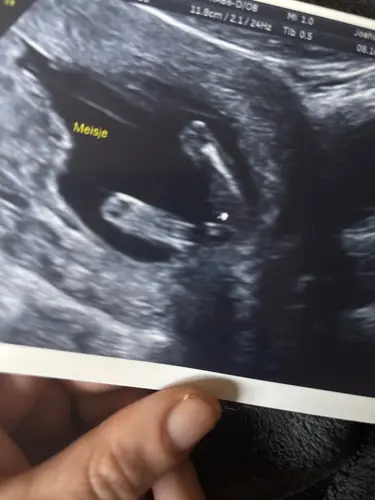

Bij mn vorige zwangerschsp heb ik met 14 weken precies een geslachtsbepaling gehad. De echoscopiste gaf aan met 100% zekerheid te kunnen zeggrn dat het een meisje was. Ik zag dit zelf ook en het klopte. Dus het kan wel gewoon goed gaan.

Ik lees ook even mee. Ik heb met 13+3 de 13-weken echo gehad. De echoscopiste weet voor 80% zeker wat het geslacht is. Bij mijn vorige zwangerschap had ik ook met 13+3 de 13 weken echo. Via de nub heb ik toen gezien dat het een jongetje is. (En gevraagd in groepen) Dat is ook zo gebleven. Ik wil me nog niet helemaal vastklampen aan die 80%. Over 2 weken met 16+3 een geslachtsecho. 20% kans dat het nog veranderd. Ik vraag me ook af hoevaak dat dan voorkomt dat het nog veranderd.

Ze zeggen dat de witte streep vaak het schaambot is dus daar zou je het meisje wel aan kunnen herkennen